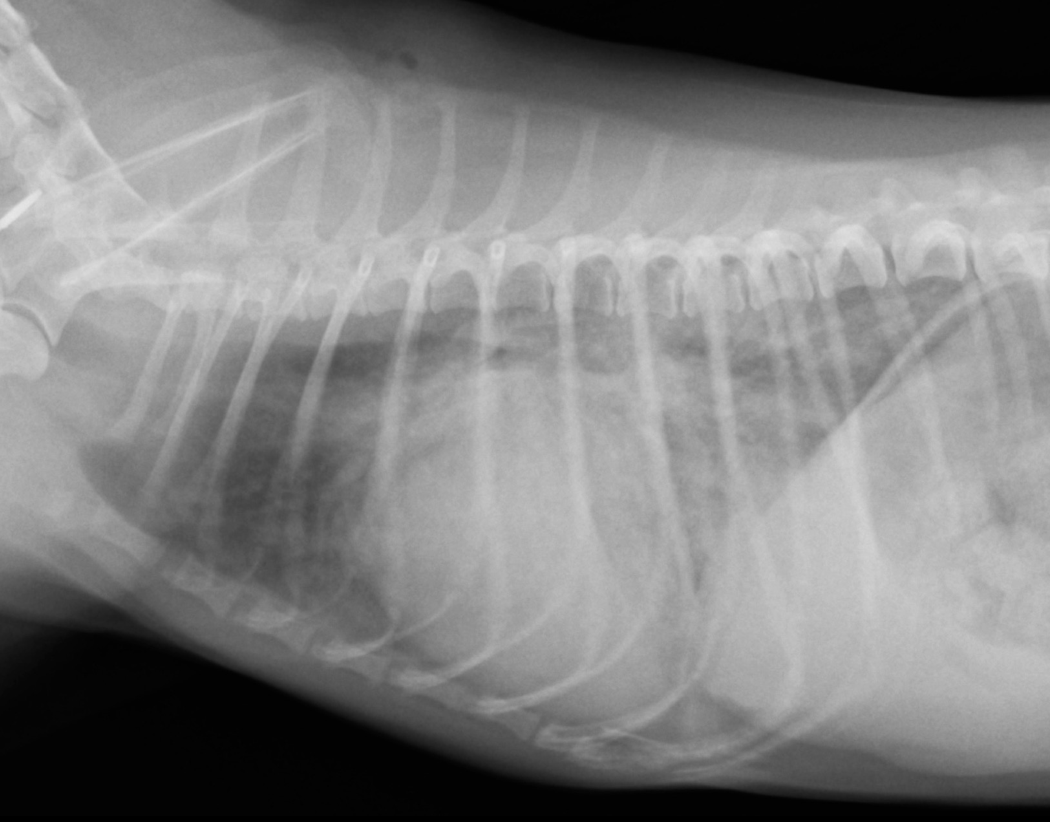

・レントゲン検査: 肺に水分がたまっているかを確認し、心臓の大きさや形も評価します。